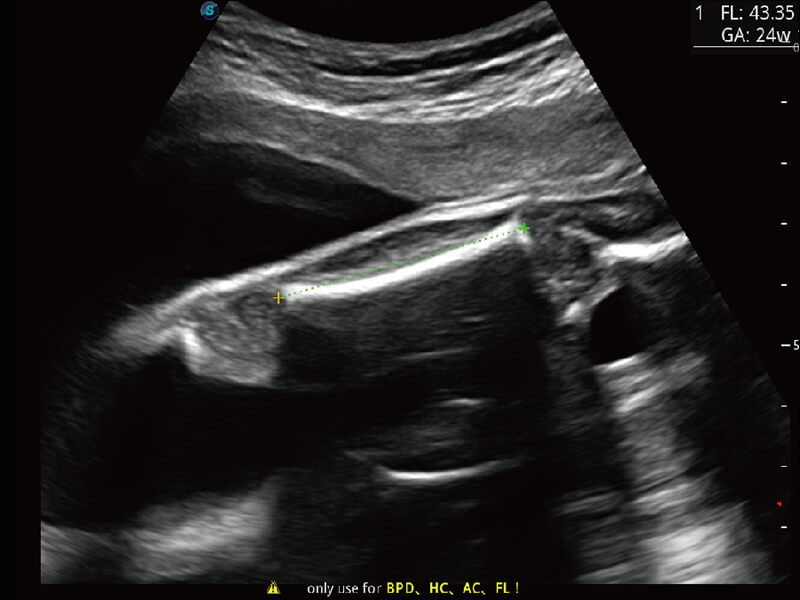

S60探头工艺,从前端信号处理每一个环节采集无损声学数据,真实还原组织原貌,再现解剖细节。